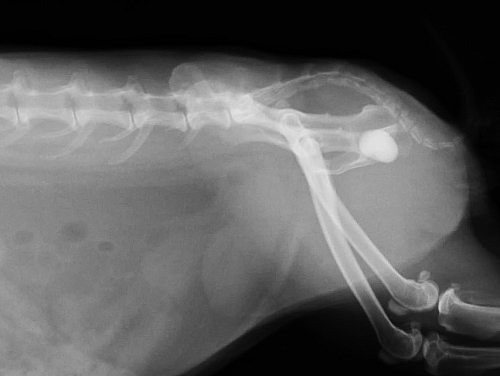

下の写真は膀胱結石が尿道結石となり尿路閉塞を生じた一連の変化をレントゲンで撮影したものです。数週間にわたる血尿と「排尿時のしぶり」と頻回尿を症状とする排尿障害を起こしていたウサギのものです。レントゲン検査では1cm程の膀胱結石が確認されました。

膀胱炎にやそれに伴う頻尿などの諸症状に対する対症療法を行ってもあまり症状の改善がみられないため、手術を計画しましたが、その前に排尿困難に陥って緊急で来院した際のレントゲン写真が下の二枚です。膀胱内にあった結石が尿道結石となり急性の尿路閉塞を生じています。

このように上流でつくられた結石が下流へ流れ、そこで急性の尿路閉塞を生じるということが、尿路結石症の最も激しい症状を引き起こします。尿路閉塞に対しては結石の閉塞状態をはじめ、腎機能の評価をはじめとする全身の評価と緊急手術を含めた閉塞解除に関わる治療を並行して迅速に行わなければなりません。

上写真のウサギは緊急の尿道切開術によって尿道結石の摘出を実施いたしました。